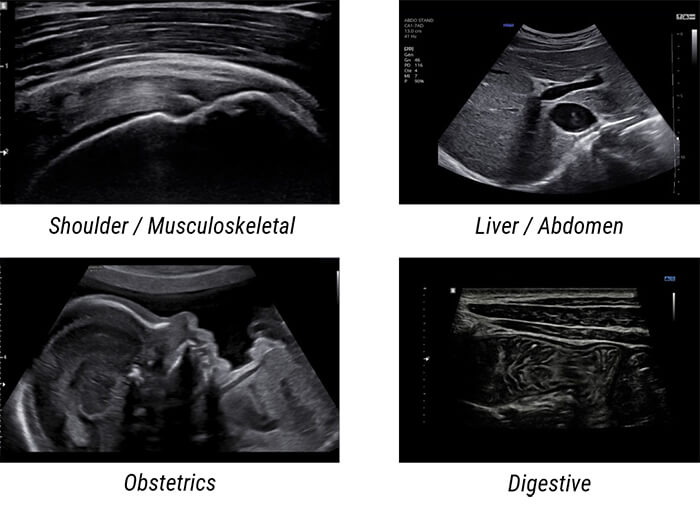

Examples of Images: The gray levels reflect variations in the texture of the internal organs as shown in these 4 different clinical images.